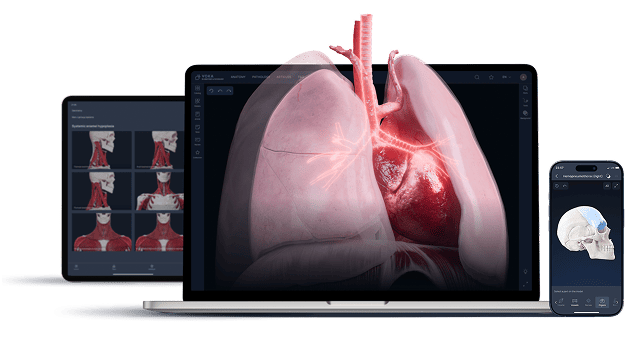

Medisinsk utdanning

Gi medisinstudenter 3D-anatomiske modeller og interaktive AR-opplevelser som gjør det enklere å visualisere og huske komplekse strukturer.